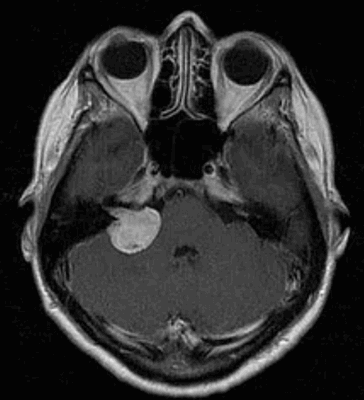

Наиболее информативным методом выявления вестибулярных шванном является МРТ головного мозга с контрастным усилением в режиме Т1 и Т2. Это исследование позволяет определить размеры опухоли, наличие перитуморозного отека, наличие признаков окклюзионной гидроцефалии, которая может быть следствием сдавления опухолью IV желудочка. Кроме этого МРТ позволяет провести дифференциальную диагностику с другими опухолями схожей локализации (чаще с менингиомой задней грани пирамиды височной кости). Еще одним стандартом диагностики является КТ в костном режиме. Независимо от снижения слуха стандартом является проведение аппаратной аудиографии.

В работе проведен анализ результатов обследования и хирургического лечения 90 пациентов с верифицированными вестибулярными шванномами преимущественно больших размеров, оперированных в РНХИ им. проф. А.Л. Поленова с 2013 г. по 2014 г. Нами заложено два основных направления в нашей работе - это хирургическое и нейрофизиологическое. Первое направление включало изучение топографо-анатомического варианта опухоли, распространенность новообразования и степень ее биологической агрессивности. Любое хирургическое вмешательство тщательно планировалось с использованием современных методов нейровизуализации, позволяющих оценить взаимоотношение опухоли с магистральными сосудами и краниальными нервами. Задачами хирургии является сочетание максимальной радикальности с сохранением функции черепных нервов. При больших и гигантских шванномах использовался стандартный ретросигмовидный доступ, но с укладкой больного в сидячем положении, что обеспечивает на наш взгляд, лучший обзор опухоли, баланс ликвородинамики, меньшую тракцию полушария мозжечка и адекватную декомпрессию ствола головного мозга, непрерывное «промывание» раны как дополнительный метод гемостаза, исключающий скопление крови в ране и окклюзию цистерн. Второе направление сводилось к многофункциональному интраоперационному мониторингу. Все пациенты были разделены нами на две группы: 1-я группа - глухие, 2-я группа- с сохранным слухом. Возраст пациентов варьировал от 24 до 83 лет, средний возраст составил 45,4 ± 3,2 г. Отмечено преобладание женщин - 71 (78,8 %), мужчин - 19 (21,1 %). Преимущественное расположение опухоли было правосторонним - 62 (68,8 %), левосторонним - 28 (31,1 %). Длительность заболевания колебалась от 1 года до 17 лет. Размеры опухоли определялись по данным КТ и/или МРТ. Размеры опухоли варьировались от 25 мм до 42,1 мм. В первую группу (глухие) вошли - 70 (77,8 %) пациентов, во вторую группу (с сохранным слухом) - 20 (22,2 %) пациентов. В нашей работе мы использовали общепринятые классификации вестибулярных шванном (Koos, M. Sammi). У большинства пациентов, поступающих в стационар, выявлены вестибулярные шванномы больших и гигантских размеров (Koos IV). Причины этого явления весьма разнообразны и требуют отдельного целенаправленного исследования. Радикальность удаления опухоли оценивалась по Токийской классификации (1998 г.). Всем пациентам проводился дооперационный диагностический стандартный клинический комплекс, включающий в себя: неврологическое, отоневрологическое, нейроофтальмологическое, нейрофизиологическое обследование. У пациентов с сохранным слухом проводили в дооперационном периоде аудиометрию, подтверждающую и определяющую степень сохранности слуха по шкале Gardner-Robertson [4, 5, 6]. Функцию лицевого нерва при поступлении и в раннем послеоперационном периоде оценивали по шкале House-Brackmann [5, 6, 7]. Тяжесть состояния в момент поступления в отделение и при выписке оценивали по шкале Karnofsky. У 2 (2,2 %) больных состояние оценивалось в 50 %, в 60-70 % у 45 пациентов (женщин - 42 (46,6 %); мужчин - 3 (3,3 %)), в 80-90 % (мужчин - 15 (16,6 %), женщин - 28 (31,1 %)).